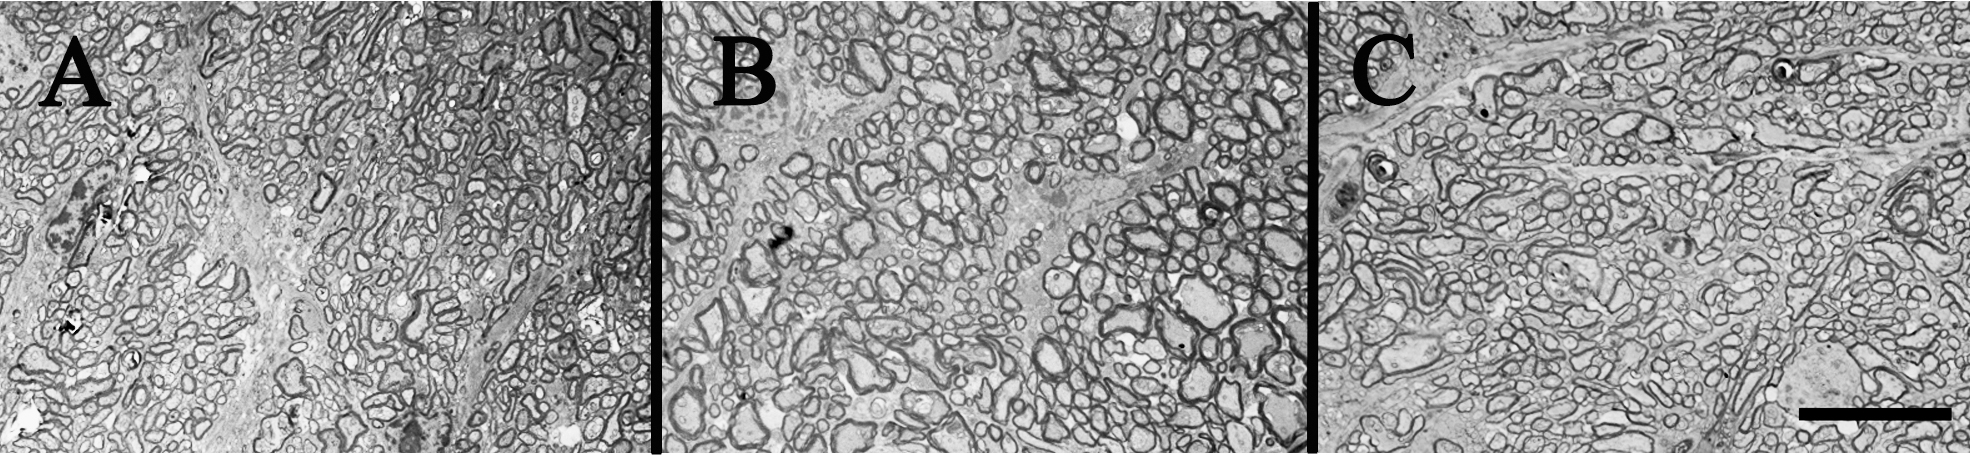

Figure 3. Diabetic and nondiabetic mouse optic nerves. A, B, and C show electron micrographs of diabetic and nondiabetic mouse optic nerves. No differences in axon density were observed between

groups. Experimental groups referred to in this figure are: A; Nondiabetic (N), B; Diabetic-STZ (D STZ), and C; Diabetic-Ins2Akita (D Ins2Akita). Scale bar=10 µm.